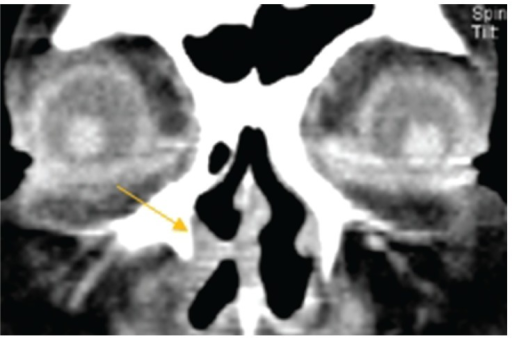

- 누도조영술 (dacryocystography): 폐쇄 위치 확인

- CT/MRI: 종양 감별